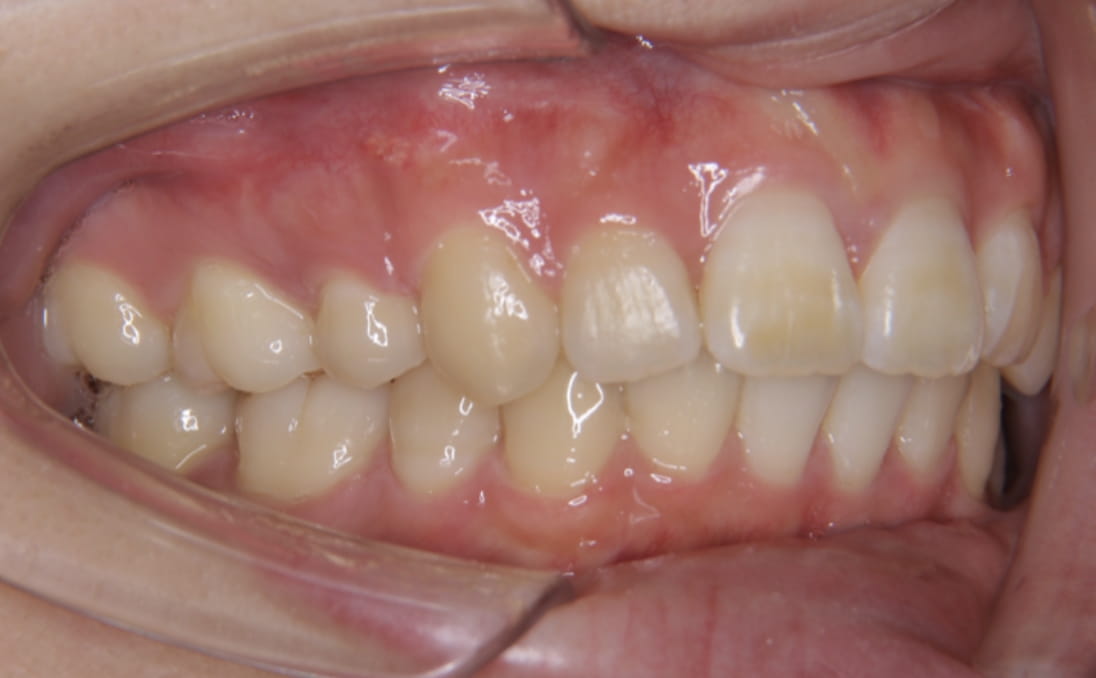

《歯槽性上下顎前突を伴う叢生》

症例42

性別:女性 年齢:13歳 お住まいの地域:奈良市

主訴 上の2本が出てるのが気になる

治療装置 上裏側、下表側からのハーフリンガル矯正装置

抜歯 上下4本

治療期間 2年8ヶ月

診断名 歯槽性上下顎前突を伴う叢生

副作用 歯肉退縮・歯根吸収・歯髄壊死・癒着による予期せぬ歯の動き

より綺麗にする希望を達成するために上下4本を抜歯。前歯のリトラクション(後方移動)を行うためにインプラントを使用。若年層ではあるが、インプラントの安定がよく、ヘッドギアに切り替えることなく、順調に進められた。

治療前